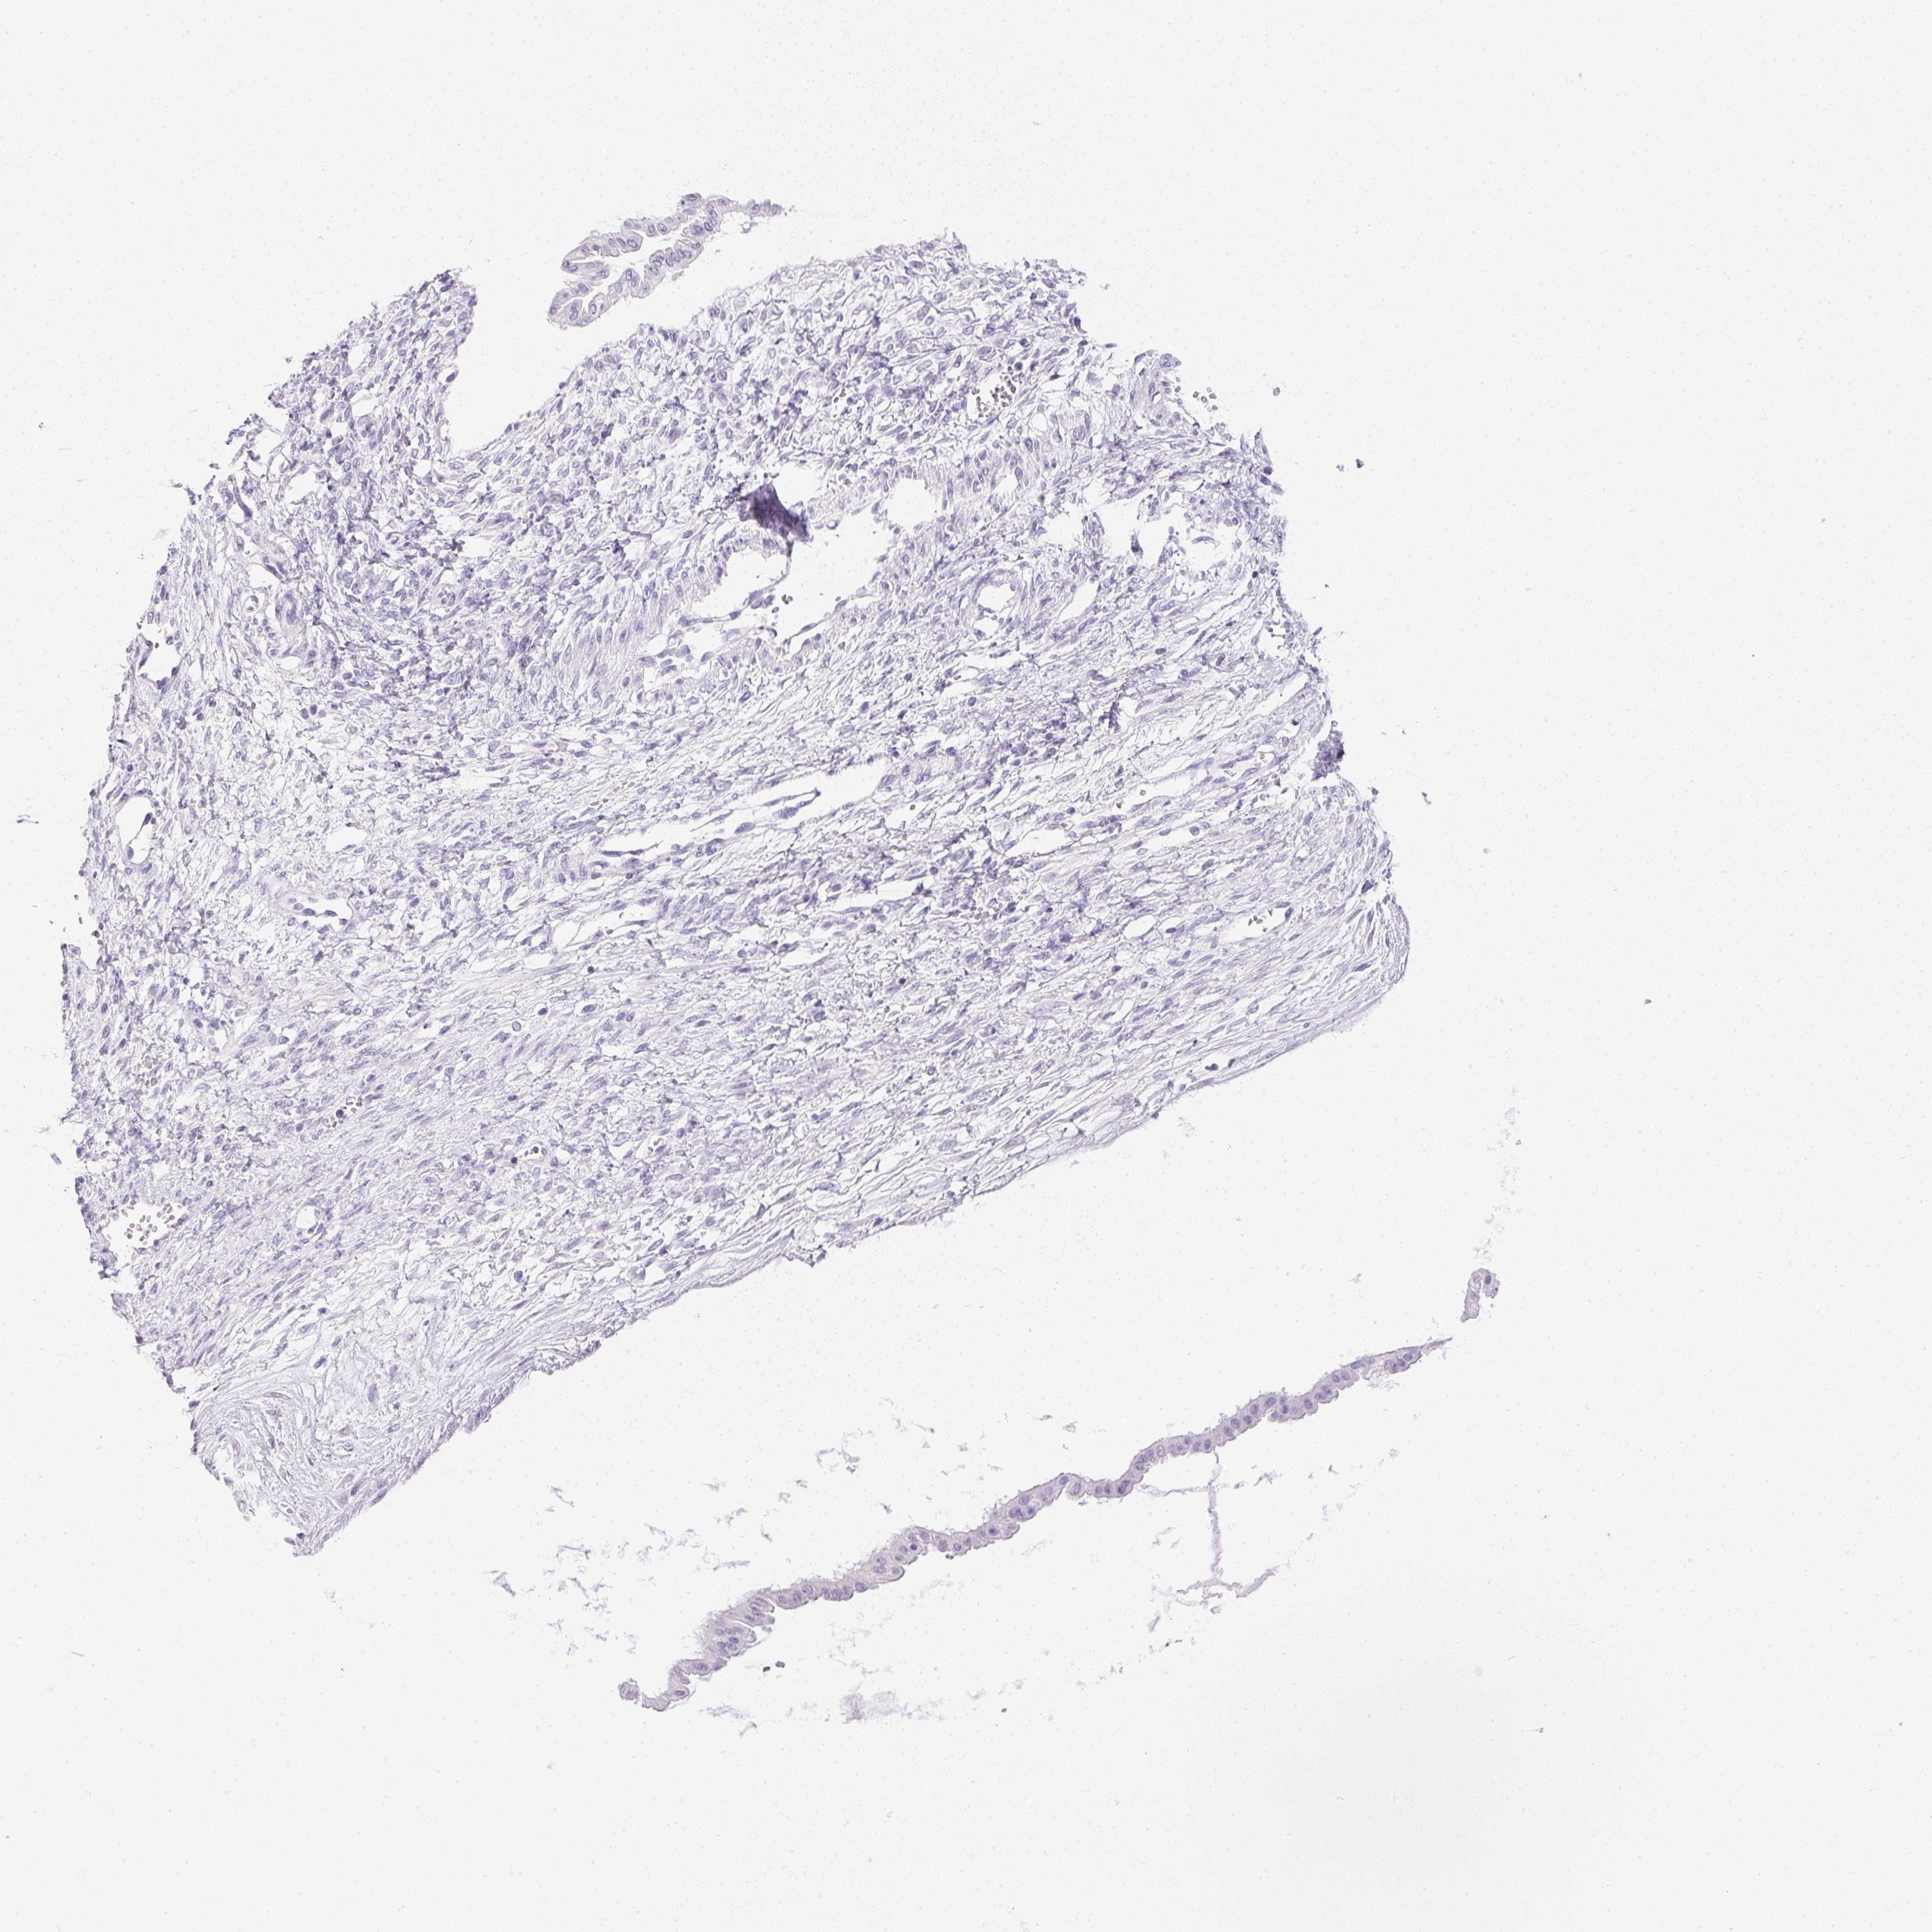

OVARIAN CANCER - Protein expressioni

A mouse-over function shows sample information and annotation data. Click on an image to view it in a full screen mode. Samples can be filtered based on level of antibody staining by selecting one or several of the following categories: high, medium, low and not detected. The assay and annotation is described here.

Note that samples used for immunohistochemistry by the Human Protein Atlas do not correspond to samples in the TCGA dataset.

Antibody stainingi

Antibody staining in the annotated cell types in the current human tissue is reported as not detected, low, medium, or high, based on conventional immunohistochemistry profiling in selected tissues. This score is based on the combination of the staining intensity and fraction of stained cells.

Each image is clickable and will lead to virtual microscopy that enables deeper exploration of all samples and also displays staining intensity scores, fraction scores and subcellular localization as well as patient and tissue information for each sample.

Antibody HPA038069